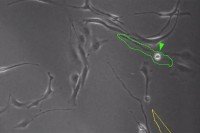

black and white image of cells under a microscope

Researchers Discover Stem Cells That May Drive Aggressive Behavior in Glioblastoma

Researchers have discovered uncanny similarities between cells found in brain tumors and a type of stem cell that’s important for building the brain during fetal development.